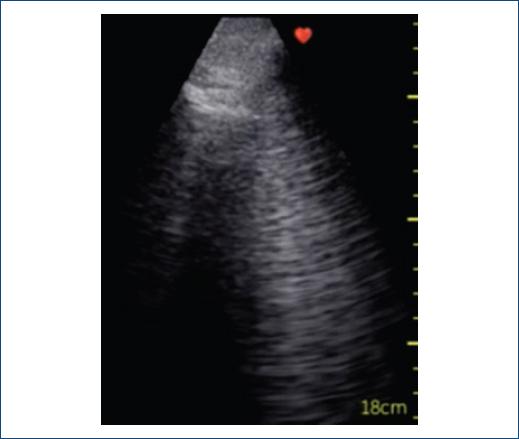

Figura 1 Ultrasonido pulmonar que muestra múltiples líneas B confluentes y patrón en vidrio despulido en un paciente con diagnóstico de neumonía intersticial.

Si bien la literatura es escasa, los hallazgos reportados incluyen engrosamiento pleural, pleura irregular, patrón de líneas B (Fig. 1), confluente y en vidrio despulido, consolidados basales y finalmente en algunos casos derrame pleural7-10.